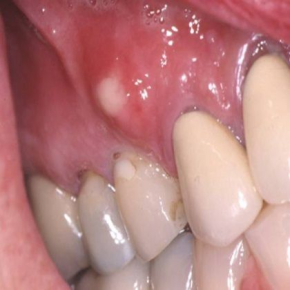

A Dental abscess is more than just a toothache—it’s a serious infection that requires prompt care. In this blog, we’ll break down what a dental abscess is, how to recognize it, and what to do if you suspect you have one. 📸 What Does a Dental Abscess Look Like? A dental abscess often appears as a swollen, pus-filled bump near the tooth or gum. You might also notice redness, facial swelling, or even a visible pocket of infection. 🧠 What Is a Dental Abscess? A dental abscess is a localized infection caused by bacteria that invade the tooth or surrounding tissues. There are three main types: These infections typically develop when bacteria enter through untreated cavities, cracks, or gum disease. ⚠️ Common Symptoms Dental abscesses can escalate quickly. Watch for these signs: In severe cases, the infection can spread beyond the tooth, which becomes a medical emergency. 🦠 What Causes It? The main culprit is bacterial infection, often due … [Read more...]